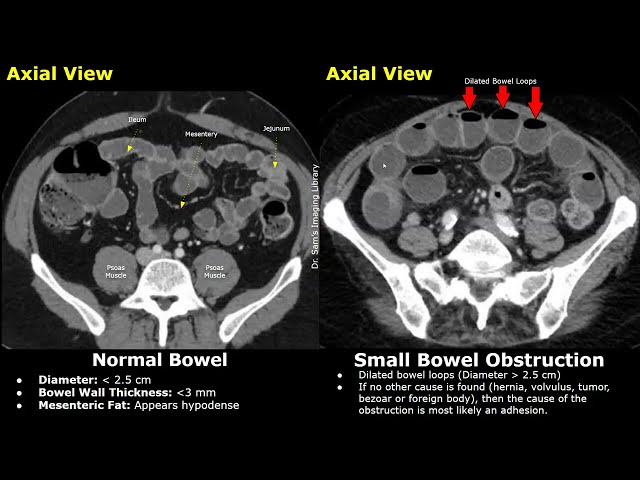

Explore core radiology concepts, imaging techniques, and interventional procedures with real-world case studies and expert insights. Learn from leading institutions like Yale and Stanford through engaging YouTube tutorials, perfect for beginners and aspiring healthcare professionals seeking practical, up-to-date knowledge.